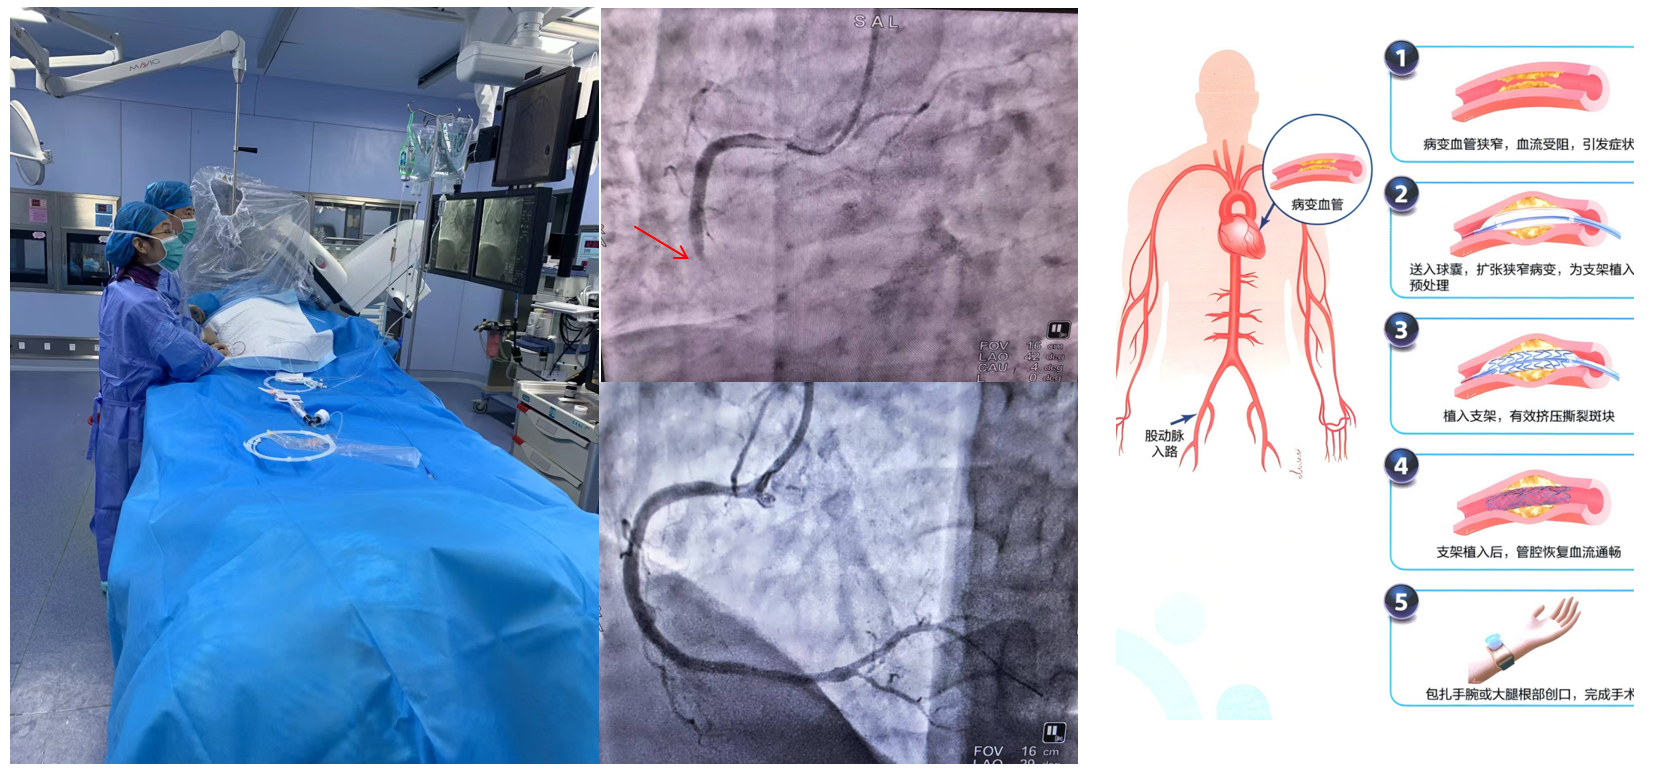

1.經皮冠狀動脈介入治療(PCI):是用心臟導管技術疏通狹窄甚至閉塞的冠狀動脈管腔,從而改善心肌血流灌注的一組治療技術。在血管嚴重狹窄或閉塞病變段放置支架或藥物球囊,以保證血管長期暢通,是冠脈介入手術的主流。

適應癥:慢性穩定型冠心病、不穩定型心絞痛、非ST段抬高型急性心肌梗死、急性ST段抬高型心肌梗死、PCI術后再狹窄或并發癥。

經皮冠狀動脈介入治療(PCI)